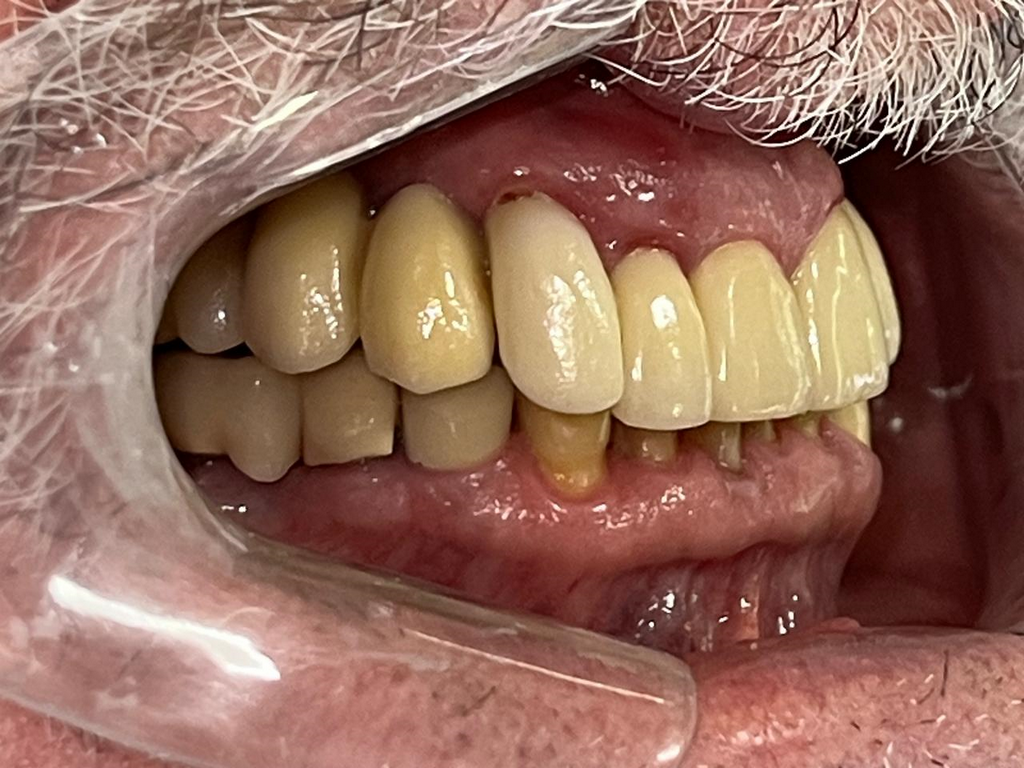

PRÓTESE TOTAL FIXA EM IMPLANTES

M.A.V.J.